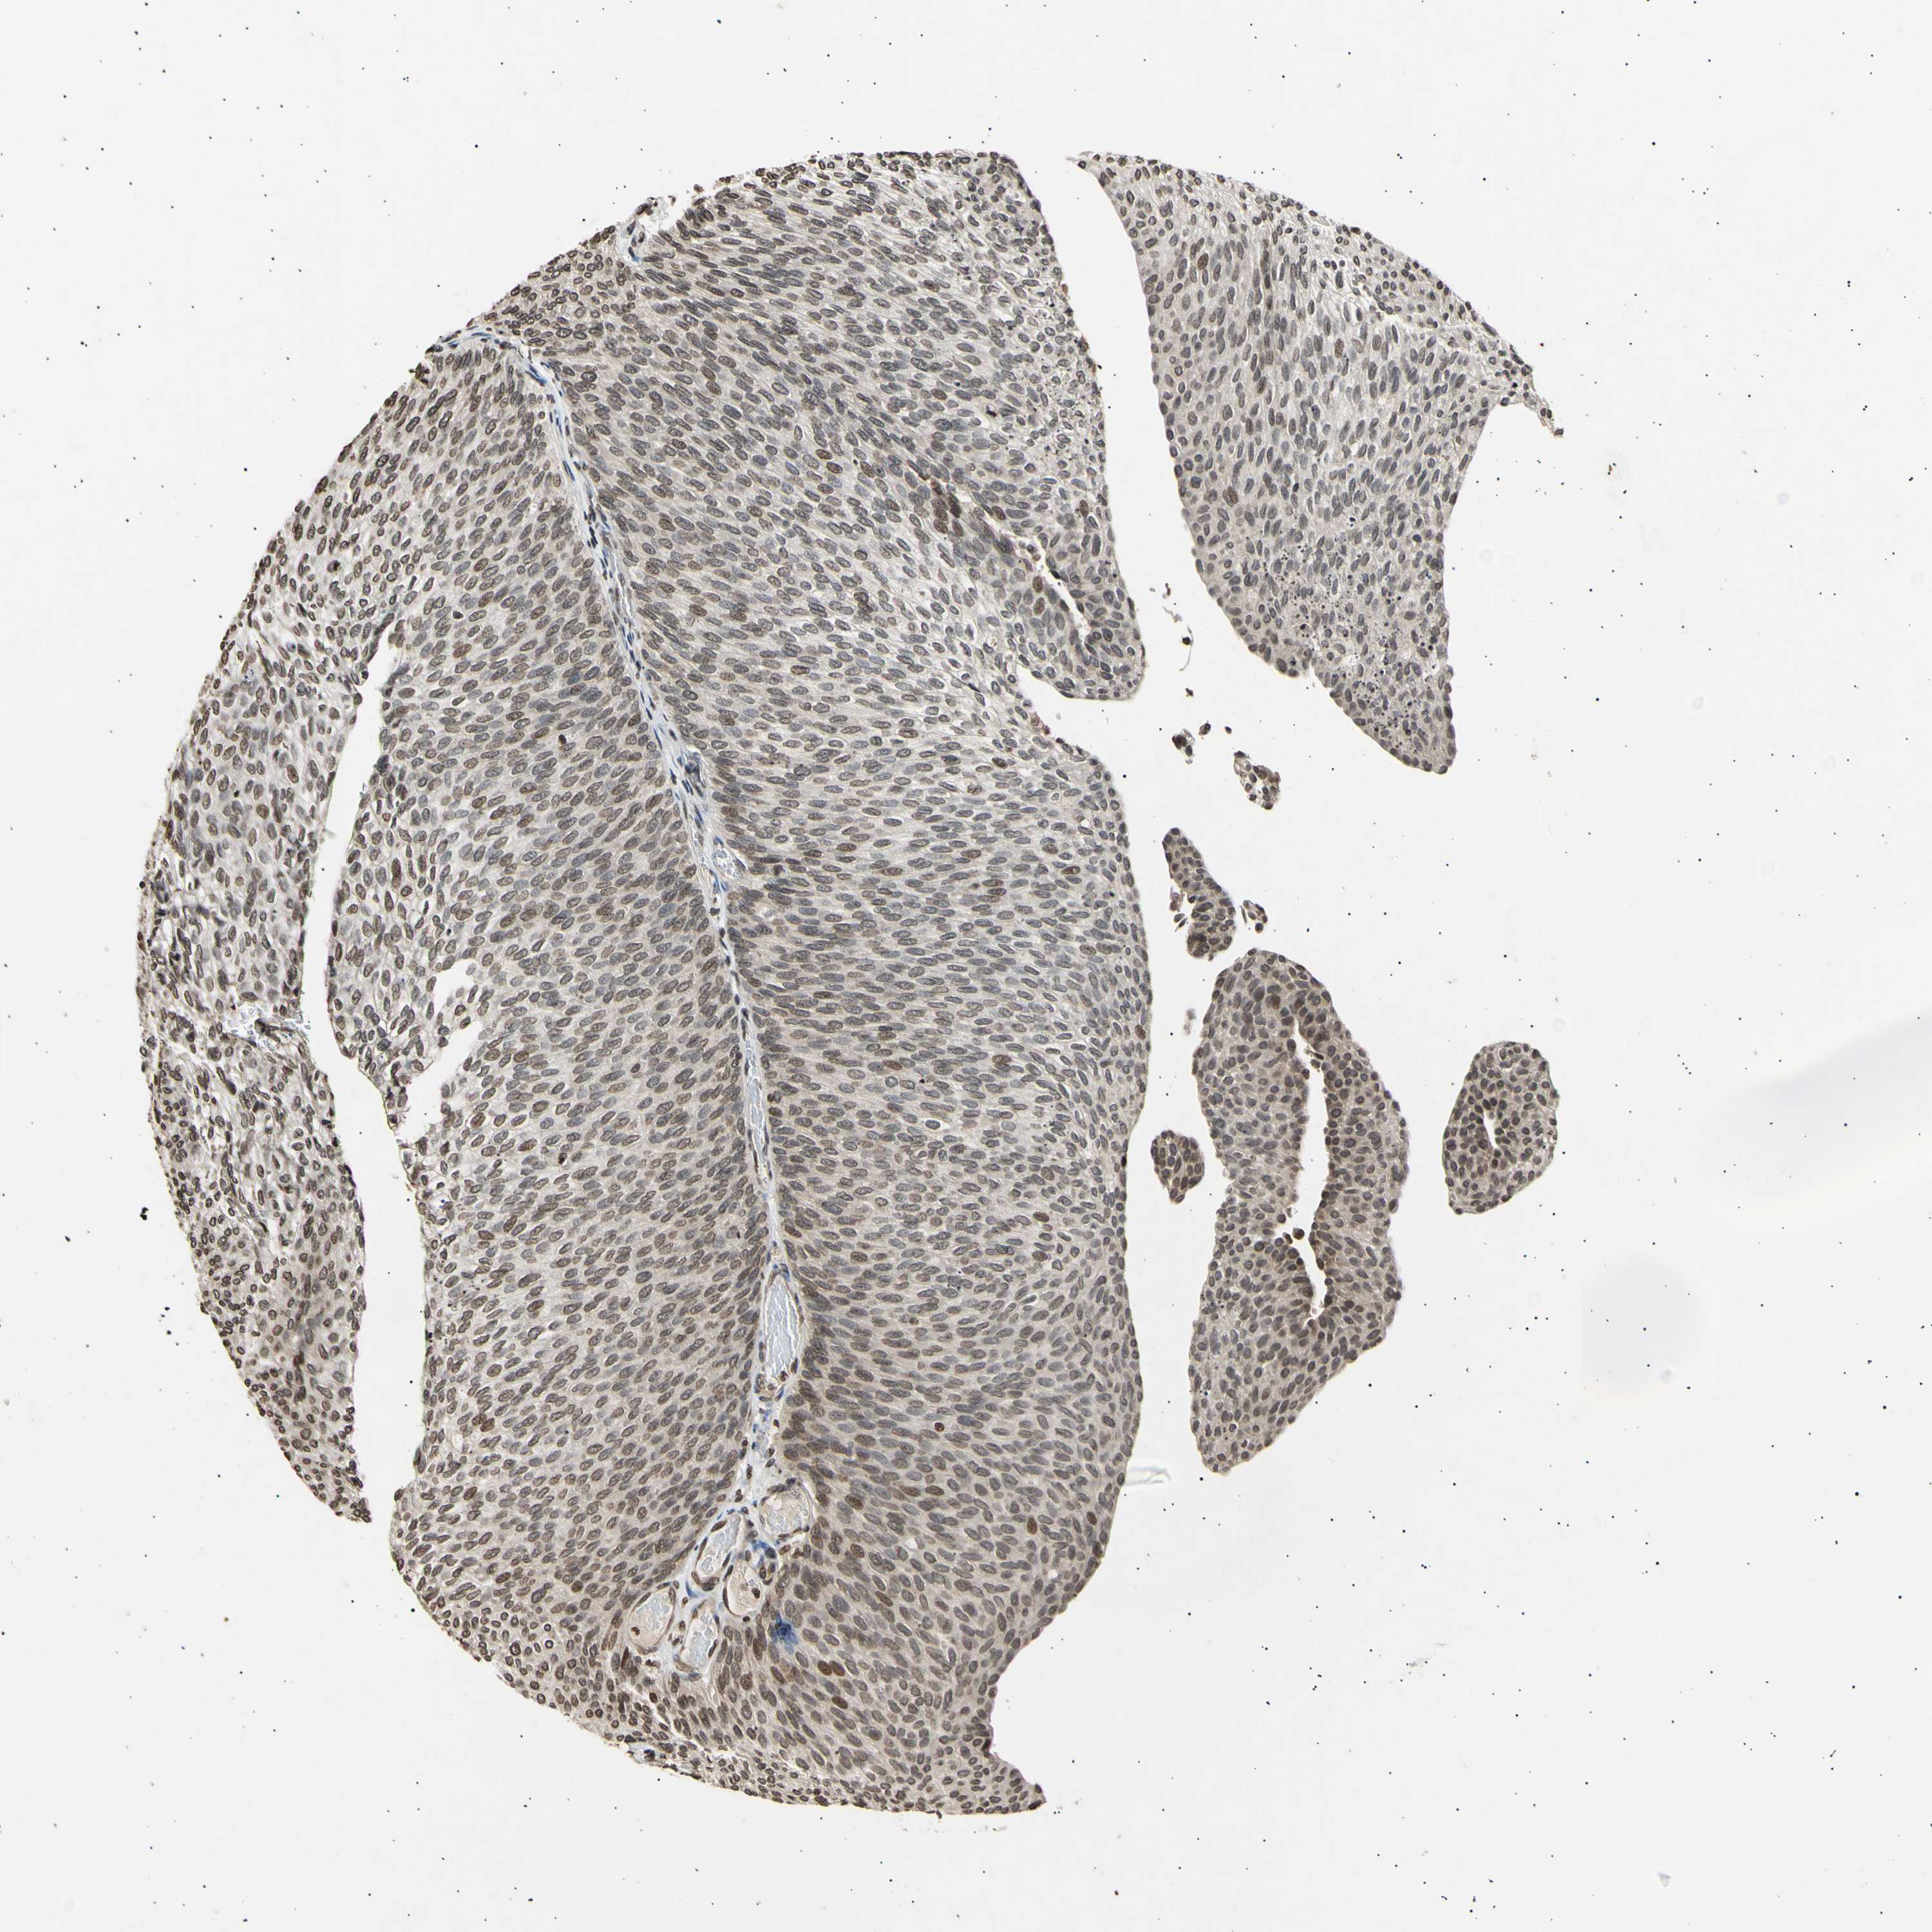

UROTHELIAL CANCER - Protein expressioni

A mouse-over function shows sample information and annotation data. Click on an image to view it in a full screen mode. Samples can be filtered based on level of antibody staining by selecting one or several of the following categories: high, medium, low and not detected. The assay and annotation is described here.

Antibody stainingi

Antibody staining in the annotated cell types in the current human tissue is reported as not detected, low, medium, or high, based on conventional immunohistochemistry profiling in selected tissues. This score is based on the combination of the staining intensity and fraction of stained cells.

Each image is clickable and will lead to virtual microscopy that enables deeper exploration of all samples and also displays staining intensity scores, fraction scores and subcellular localization as well as patient and tissue information for each sample.

Antibody CAB009567

Staining

High

Medium

Low

Not detected

Intensity

Strong

Moderate

Weak

Negative

Quantity

>75%

75%-25%

<25%

None

Location

Nuclear

Cytoplasmic/membranous

Cytoplasmic/membranous,nuclear

Urothelial carcinoma, Low grade

Urothelial carcinoma, High grade